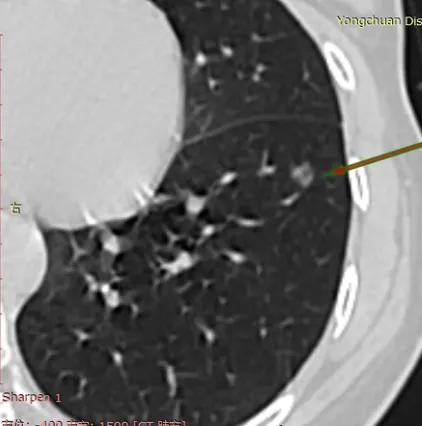

今天分享的又是一位坚强的母亲,丈夫做了肾癌手术,正需要人照顾的时候,家里还有年幼的孩子,她在体检查出8mm混合磨玻璃结节,虽然看出她自己也很焦虑,但在她向我求助的帖子中,可以看出她字里行间更多的是对家庭对孩子的担心,却没有对手术的恐惧,反而希望尽快手术让自己好起来可以回去照顾家人,可叹可敬。虽然患者是高危结节,但我看了以后肯定并不严重,只需要楔形切除小手术就可以搞定了,最后虽然大病理是浸润与我术前判断的微有一点小小的出入,但其实浸润灶非常小,只是因为腺泡为主让大病理升级了,但其实非常接近微,已经治愈了。

我是2021年10月体检发现肺部有个8MM的混杂密度结节,吃了半个月消炎药和夏枯草口服液,于2022年4月7日复查,复查结果的CT报告单没有报告这个结节,但复查医生查了他的电脑告诉我结节还在,大小感觉没变化,还说是混杂又挨到血管一定要注意,叫过半年再复查。我很担心也很紧张,我老公2017年甲状腺癌手术,2021年1月肾癌手术(右肾和右边输尿管全切),我家孩子还小,万一我又倒下了怎么办哟,孩子和老公都需要我。我不能倒下,我很焦虑。不知道我这结节如何?如果能手术我希望能快些手术。恳请戴主任百忙之中帮我看看。万分感谢!感谢可可西里和冷月教我发贴帮我截图,也希望吧友顶我上去,让戴主任看到我的帖子。谢谢大家。

很像微浸润腺癌,楔形切除小手术还可以根治,不需要任何后续治疗。

6月5日我办理的住院,7日做的手术,术后不痛也不咳,手术当天下午手脚可以在床上自由活动,如果不是插了尿管感觉我手术当天就能下床活动,手术第二天我可以独立上下床(我隔壁床的病友下午2点过出手术室,晚上就在手机上打麻将赢钱钱)。我发了视频给家人朋友,她们都认为我们做了一个假手术。但是,我的大病理结果升级了,少了微,浸润了,新桥CT报告结节7mm*5mm,平均CT值—400多,实占比约50%。大病理60%腺泡+40%贴壁,浸润了。尽管是1A1,但不再如微浸润根治了,我好紧张。我家孩子还小,我老公又生病,我不怕死,只是担心万一我和我老公都不在了孩子怎么办?我做了基因检查,还没拿到结果,也是一直担心。昨天我老公告诉我他肚子有点不舒服,我问他是不是要复查了(他三月复查一次)紧张的原因。然后我们谈起,我和他现在都生病了很不幸,但如果先死的那人可能还是相对幸运的,至少有另一半照顾终老………

非常接近微,其实浸润灶比微还小,只是以腺泡为主,所以浸润。也一样根治了。